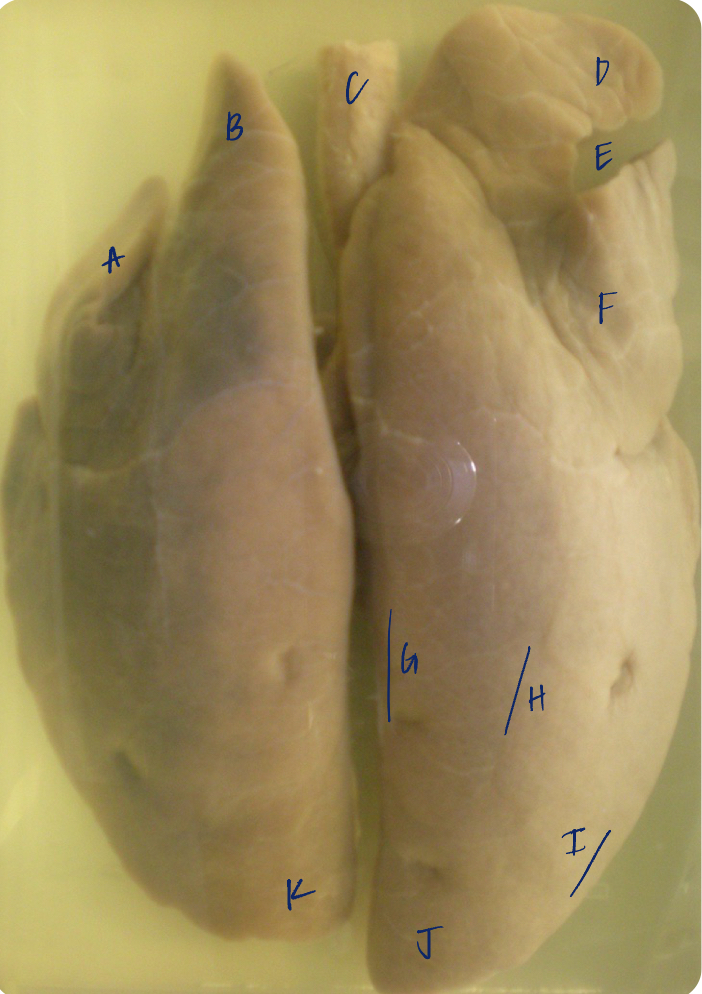

A

(dog lungs, dorsal)

L cranial lobe

B

(dog lungs, dorsal)

cranial segment, L cranial lobe

C

(dog lungs, dorsal)

caudal segment, L cranial lobe

D

(dog lungs, dorsal)

apex

E

(dog lungs, dorsal)

trachea

F

(dog lungs, dorsal)

R cranial lobe

G

(dog lungs, dorsal)

middle lobe

H

(dog lungs, dorsal)

R caudal lobe

I

(dog lungs, dorsal)

accessory lobe

J

(dog lungs, dorsal)

L caudal lobe